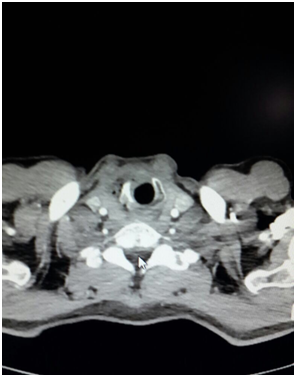

1 year ago, a 52year old male patient was diagnosed T3 glottic cancer and he did not consent to operation and he was underwent radiotherapy of the neck region due to lymph node metastasis (Figure 1). About four months after radiotherapy, halithosis and difficulty in breathing occurred and ear nose throat department planned tracheostomy (Figure 2). Patient had cachectic appearance and anaerobic odor was present. Preoperative SpO2: 82%, blood presure: 140/80 mm/Hg and heart rate: 110 beats/min. In anesthesia induction, 2mg/kg propofol, 0.6mg/kg rocuronium (Esmeron, Schering Plough, Turkey) and 1.5mcg/kg fentanyl (Talinat, Vem, Turkey) were administered. After oxygen saturation value was increased from 82% to 98% with mask ventilation, suspension blade was placed. In endoscopy, it was observed that right side of trachea was necrotic in subglottic region and necrosis extended towards strap muscles (Figure 3). While necrotic areas are cleaned, desaturation was prevented by 100% O2 18 lt/min. flow insufflations. During skin incision for tracheostomy, intubation was made carefully with endoscopy. At the level of 2nd and 3rd rings of trachea, necrotic areas at right lateral were excised and cannula was placed. In the meantime biopsy was taken and tumor didn’t occur in the biopsy result. Patient was awakened without any complications and transferred to clinic.